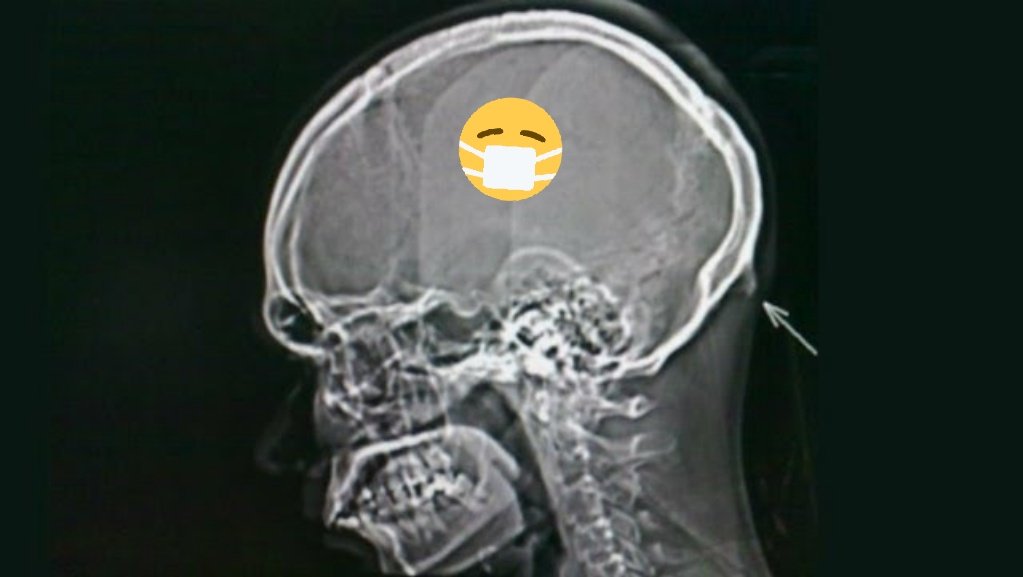

Έρευνα που δημοσιεύθηκε στο Scientific Reports συμπεραίνει ότι οι κερατόμορφες οσφυϊκές διαφοροποιήσεις που παρατηρούνται ολοένα και περισσότερο στους νέους ηλικίας 18 με 30 ετών, προκαλούνται από την εμπρόσθια κλίση του κεφαλιού, η οποία μετατοπίζει το βάρος από τη σπονδυλική στήλη στους μύες που βρίσκονται στο πίσω μέρος του κρανίου, στο ύψος του αυχένα.

Λόγω της επικράτησης της ασυνήθιστης ανάπτυξης των οστών στους νεότερους πληθυσμούς, οι ερευνητές του Πανεπιστημίου της Ακτής του Ήλιου στο Κουίνσλαντ της Αυστραλίας, εκτιμούν ότι οφείλεται στη μετατόπιση της στάσης του σώματος που επιφέρει η χρήση της σύγχρονης τεχνολογίας.

Στην ανάλυσή τους, οι επιστήμονες αναφέρουν ότι τα smartphones και άλλες φορητές συσκευές, είναι οι πιο πιθανοί υπαίτιοι για την οστική αλλαγή που παρατηρείται, καθώς απαιτείται από τον εκάστοτε χρήστη να σκύψει το κεφάλι του προς τα εμπρός, προκειμένου να κοιτάξει την οθόνη.

Ο επιστήμονας Βιομηχανικής, Ντέιβιντ Σάχαρ, δηλώνει ότι το πιο εντυπωσιακό επιστημονικό εύρημα ήταν το μέγεθος των «κεράτων» τα οποία έφταναν ήδη τα 10 χιλιοστά, παρά το νεαρό της ηλικίας των συμμετεχόντων.